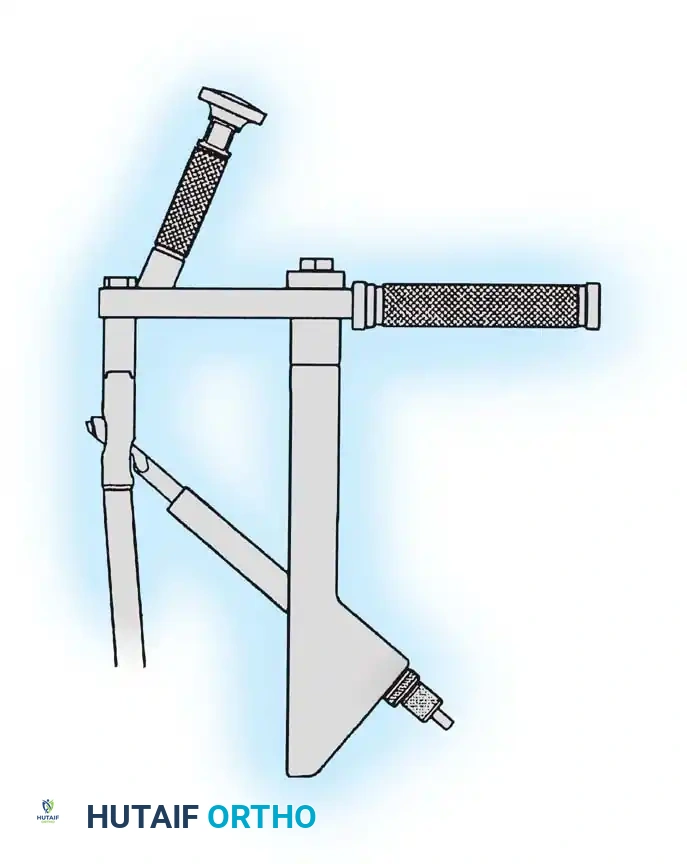

Whether using an SHS or a CMN, accurate placement of the guide wire into the femoral head is the most critical step of the operation.

Insertion of the guide wire. The wire must be positioned centrally in the femoral head on both AP and lateral views.

The Tip-Apex Distance (TAD):

Described by Baumgaertner, the TAD is the sum of the distance from the tip of the lag screw to the apex of the femoral head on both the AP and lateral radiographs. A TAD of less than 25 mm is strongly predictive of successful fixation; a TAD > 25 mm significantly increases the risk of screw cut-out.

Reaming of the femoral neck and head over the precisely placed guide wire, preparing the channel for the lag screw.

If a cephalomedullary nail is chosen, the entry point is established at the tip of the greater trochanter (or slightly medial, depending on the specific implant design).

Insertion of the cephalomedullary nail down the femoral shaft. Care must be taken not to distract the fracture site during insertion.

Proximal locking of the cephalomedullary nail. The targeting guide ensures accurate trajectory into the femoral neck.